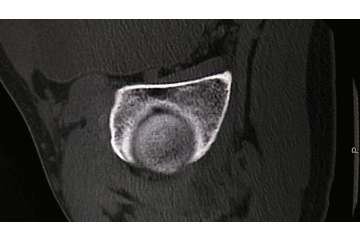

辅助检查:CT 检查提示右侧股骨颈骨皮质不连续,可见透亮骨折线及碎骨片影,断端错位、成角,周围软组织肿胀;右侧髋臼后下缘及左侧耻骨上支骨皮质不连续,断端未见明显错位;右侧髋臼后缘见类圆形稍低密度影,大小约 5*9 mm,边界清楚,边缘见硬化边;右侧髋关节在位,关节间隙未见明显变窄。

初步诊断:右股骨颈骨折(经颈型)